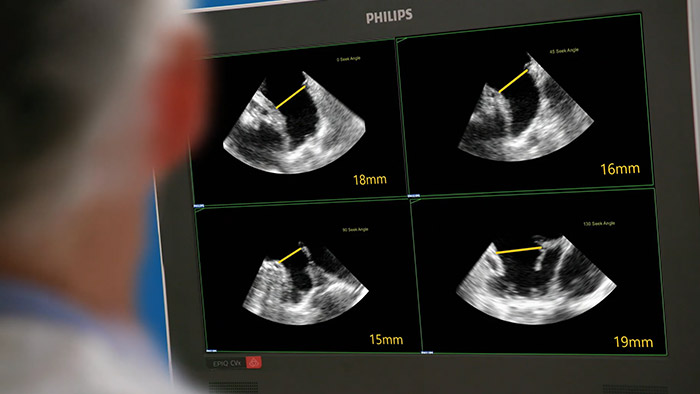

EPIQ CVxi interventionelles Ultraschallsystem

Schnelle, einfache und intuitive Beurteilung des linken Vorhofohrs. Die Philips Lösung für das linke Vorhofohr auf dem EPIQ CVxi.

• Schnelle, reproduzierbare Darstellung der Morphologie des linken Vorhofohrs und automatische Vermessung des Ostiums ausschließlich mit Ultraschall

• Mithilfe der 3D Auto LAA-Funktion kann die Messdauer im Vergleich zur manuellen Vermessung des linken Vorhofohrs um 70 % verkürzt werden*